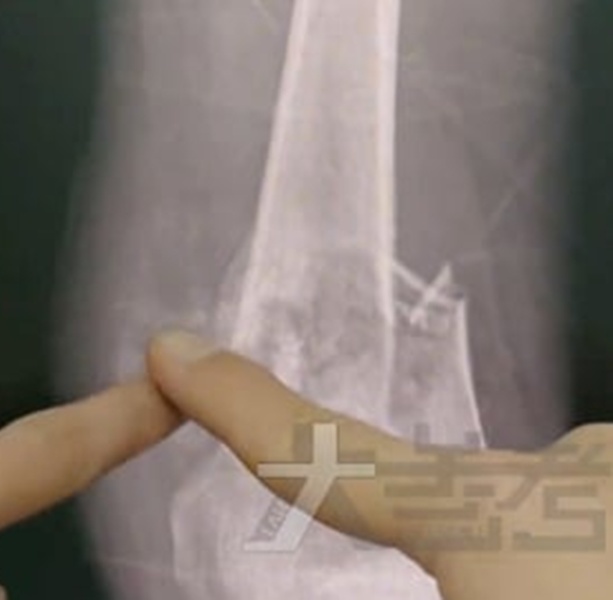

河南驻马店一名18岁高中生小乐(化名)左膝长期疼痛,起初家人以为只是缺钙或生长痛,天天补营养却未见好转。一个月后病情急速恶化,小乐就医检查才被确诊为骨肉瘤,病变范围长达12公分。

治疗期间,小乐不慎摔倒导致病理性骨折,肿瘤随创面扩散。为防癌细胞转移,医师不得不进行左腿高位截肢手术。医师表示,若不截肢,肿瘤复发和转移风险极高。手术后,小乐病情已稳定,但左腿永久截肢。